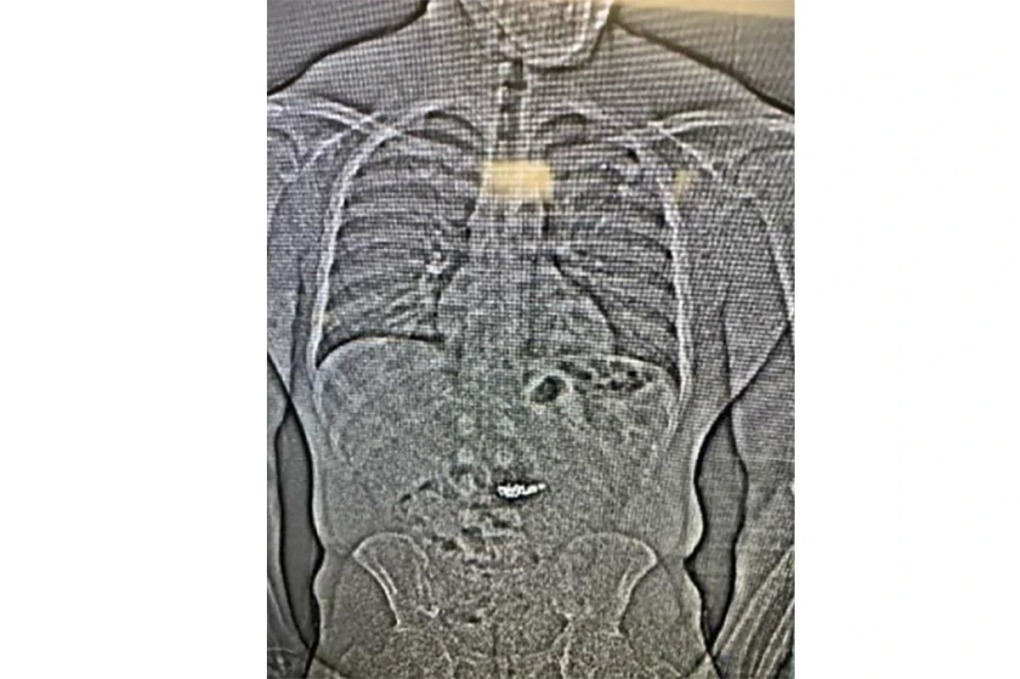

MỹKẻ cắp được cho là đă nuốt hai đôi bông tay kim cương khi bị cảnh sát truy đuổi, kết quả chụp X-quang cho thấy có vật thể lạ trong đường tiêu hóa.

Phim X-quang cho thấy vật thể lạ trong hệ tiêu hóa của Gilder. Ảnh: AP

Ảnh chụp X-quang cho thấy có vật thể lạ trong đường tiêu hóa của Gilder và giới chức nghi ngờ đây là các bông tai kim cương trị giá 770.000 USD bị cướp, nhưng cần chờ cảnh sát hạt Washington xác nhận bằng cách thu thập sau khi Gilder thải ra qua đường tiêu hóa.